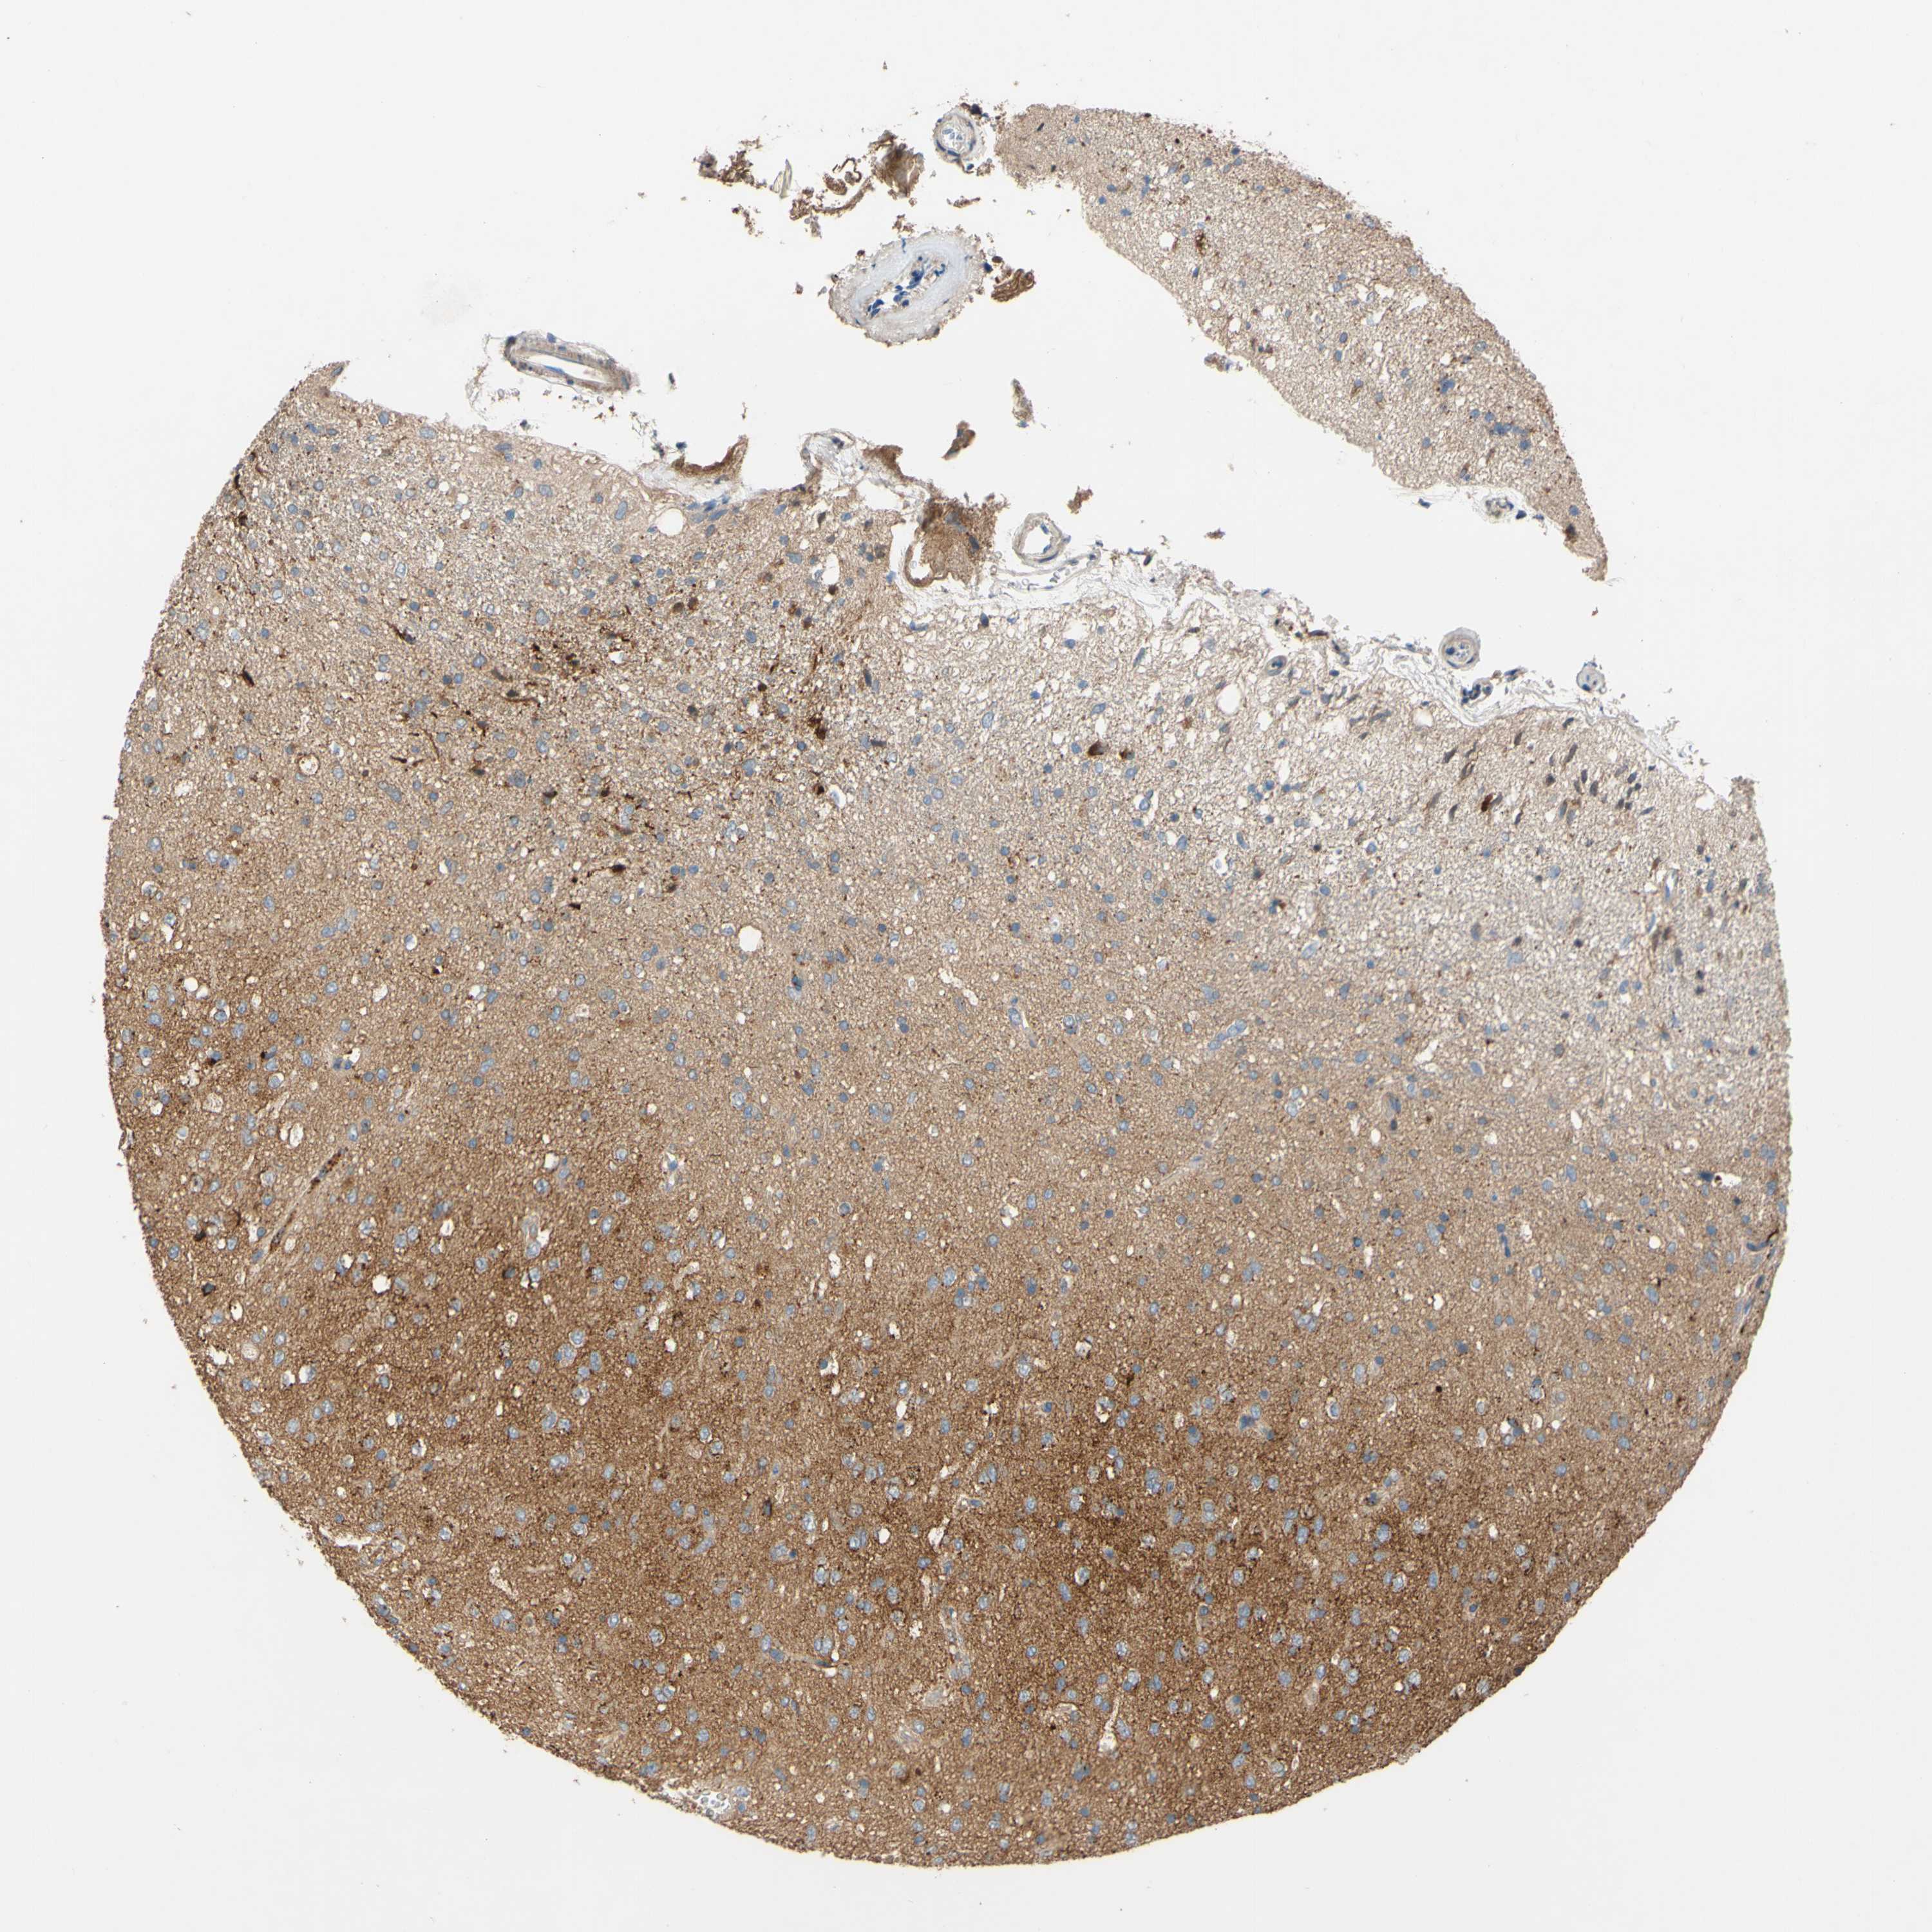

GLIOMA - Protein expressioni

A mouse-over function shows sample information and annotation data. Click on an image to view it in a full screen mode. Samples can be filtered based on level of antibody staining by selecting one or several of the following categories: high, medium, low and not detected. The assay and annotation is described here.

Note that samples used for immunohistochemistry by the Human Protein Atlas do not correspond to samples in the TCGA dataset.

Antibody stainingi

Antibody staining in the annotated cell types in the current human tissue is reported as not detected, low, medium, or high, based on conventional immunohistochemistry profiling in selected tissues. This score is based on the combination of the staining intensity and fraction of stained cells.

Each image is clickable and will lead to virtual microscopy that enables deeper exploration of all samples and also displays staining intensity scores, fraction scores and subcellular localization as well as patient and tissue information for each sample.

Antibody HPA011868

Antibody CAB024949

Staining

High

Medium

Low

Not detected

Intensity

Strong

Moderate

Weak

Negative

Quantity

>75%

75%-25%

<25%

None

Location

Nuclear

Cytoplasmic/membranous

Cytoplasmic/membranous,nuclear

Glioma, malignant, High grade

Glioma, malignant, Low grade